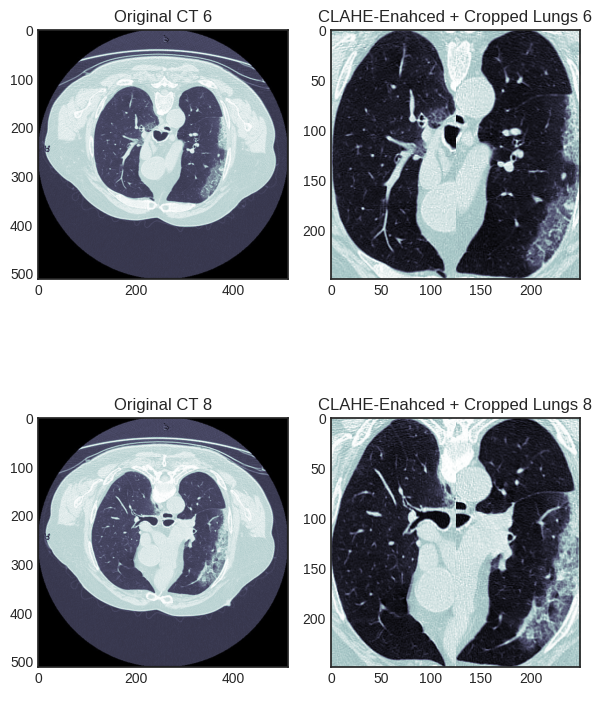

The rapid global spread of Coronavirus Disease 2019 (COVID-19) highlighted the critical need for rapid and accurate diagnostic tools to manage the pandemic and mitigate its spread. While Reverse Transcription Polymerase Chain Reaction (RT-PCR) tests were the gold standard for confirmation, their shortage during peak outbreaks necessitated alternative diagnostic methods.[1] Computed Tomography (CT) scans emerged as a valuable tool for screening and diagnosing COVID-19, as they have been shown to be more sensitive than RT-PCR tests.[2] The analysis of CT scans is a time-intensive process that requires specialized medical expertise, which can be a significant bottleneck, especially for overwhelmed healthcare systems or in underdeveloped areas. As illustrated in Figure 1, the CT scans of COVID-19 and non-COVID patients exhibit no readily apparent differences discernible without expert evaluation.

Refer to caption

Figure 1: Examples of CT scans, first two rows contain images from healthy subjects, whereas the last two rows contain images from COVID-19 patients.[4]

The second step is a meticulous region-of-interest (ROI) extraction and cropping process. This process is specifically designed to isolate the lung regions from the rest of the CT scan. It operates by first creating a binary mask of the lungs and then using contour finding algorithms to identify the two largest contours, representing the left and right lungs. Bounding boxes are then drawn around each lung. A key design choice is to crop each lung region separately and then resize both to a consistent size of 125x250 pixels before horizontally concatenating them into a single 250x250 pixel image. As shown in figure 3, this approach focuses the model exclusively on the diagnostically relevant pulmonary regions, removing extraneous information such as ribs, the heart, or background noise. By providing the model with a consistent, focused input, the feature learning process becomes more efficient and effective, which is a strong contributing factor to the final high performance.

Figure 3: CT Scans and Cropped Lung Regions of COVID-19 CT segmentation dataset